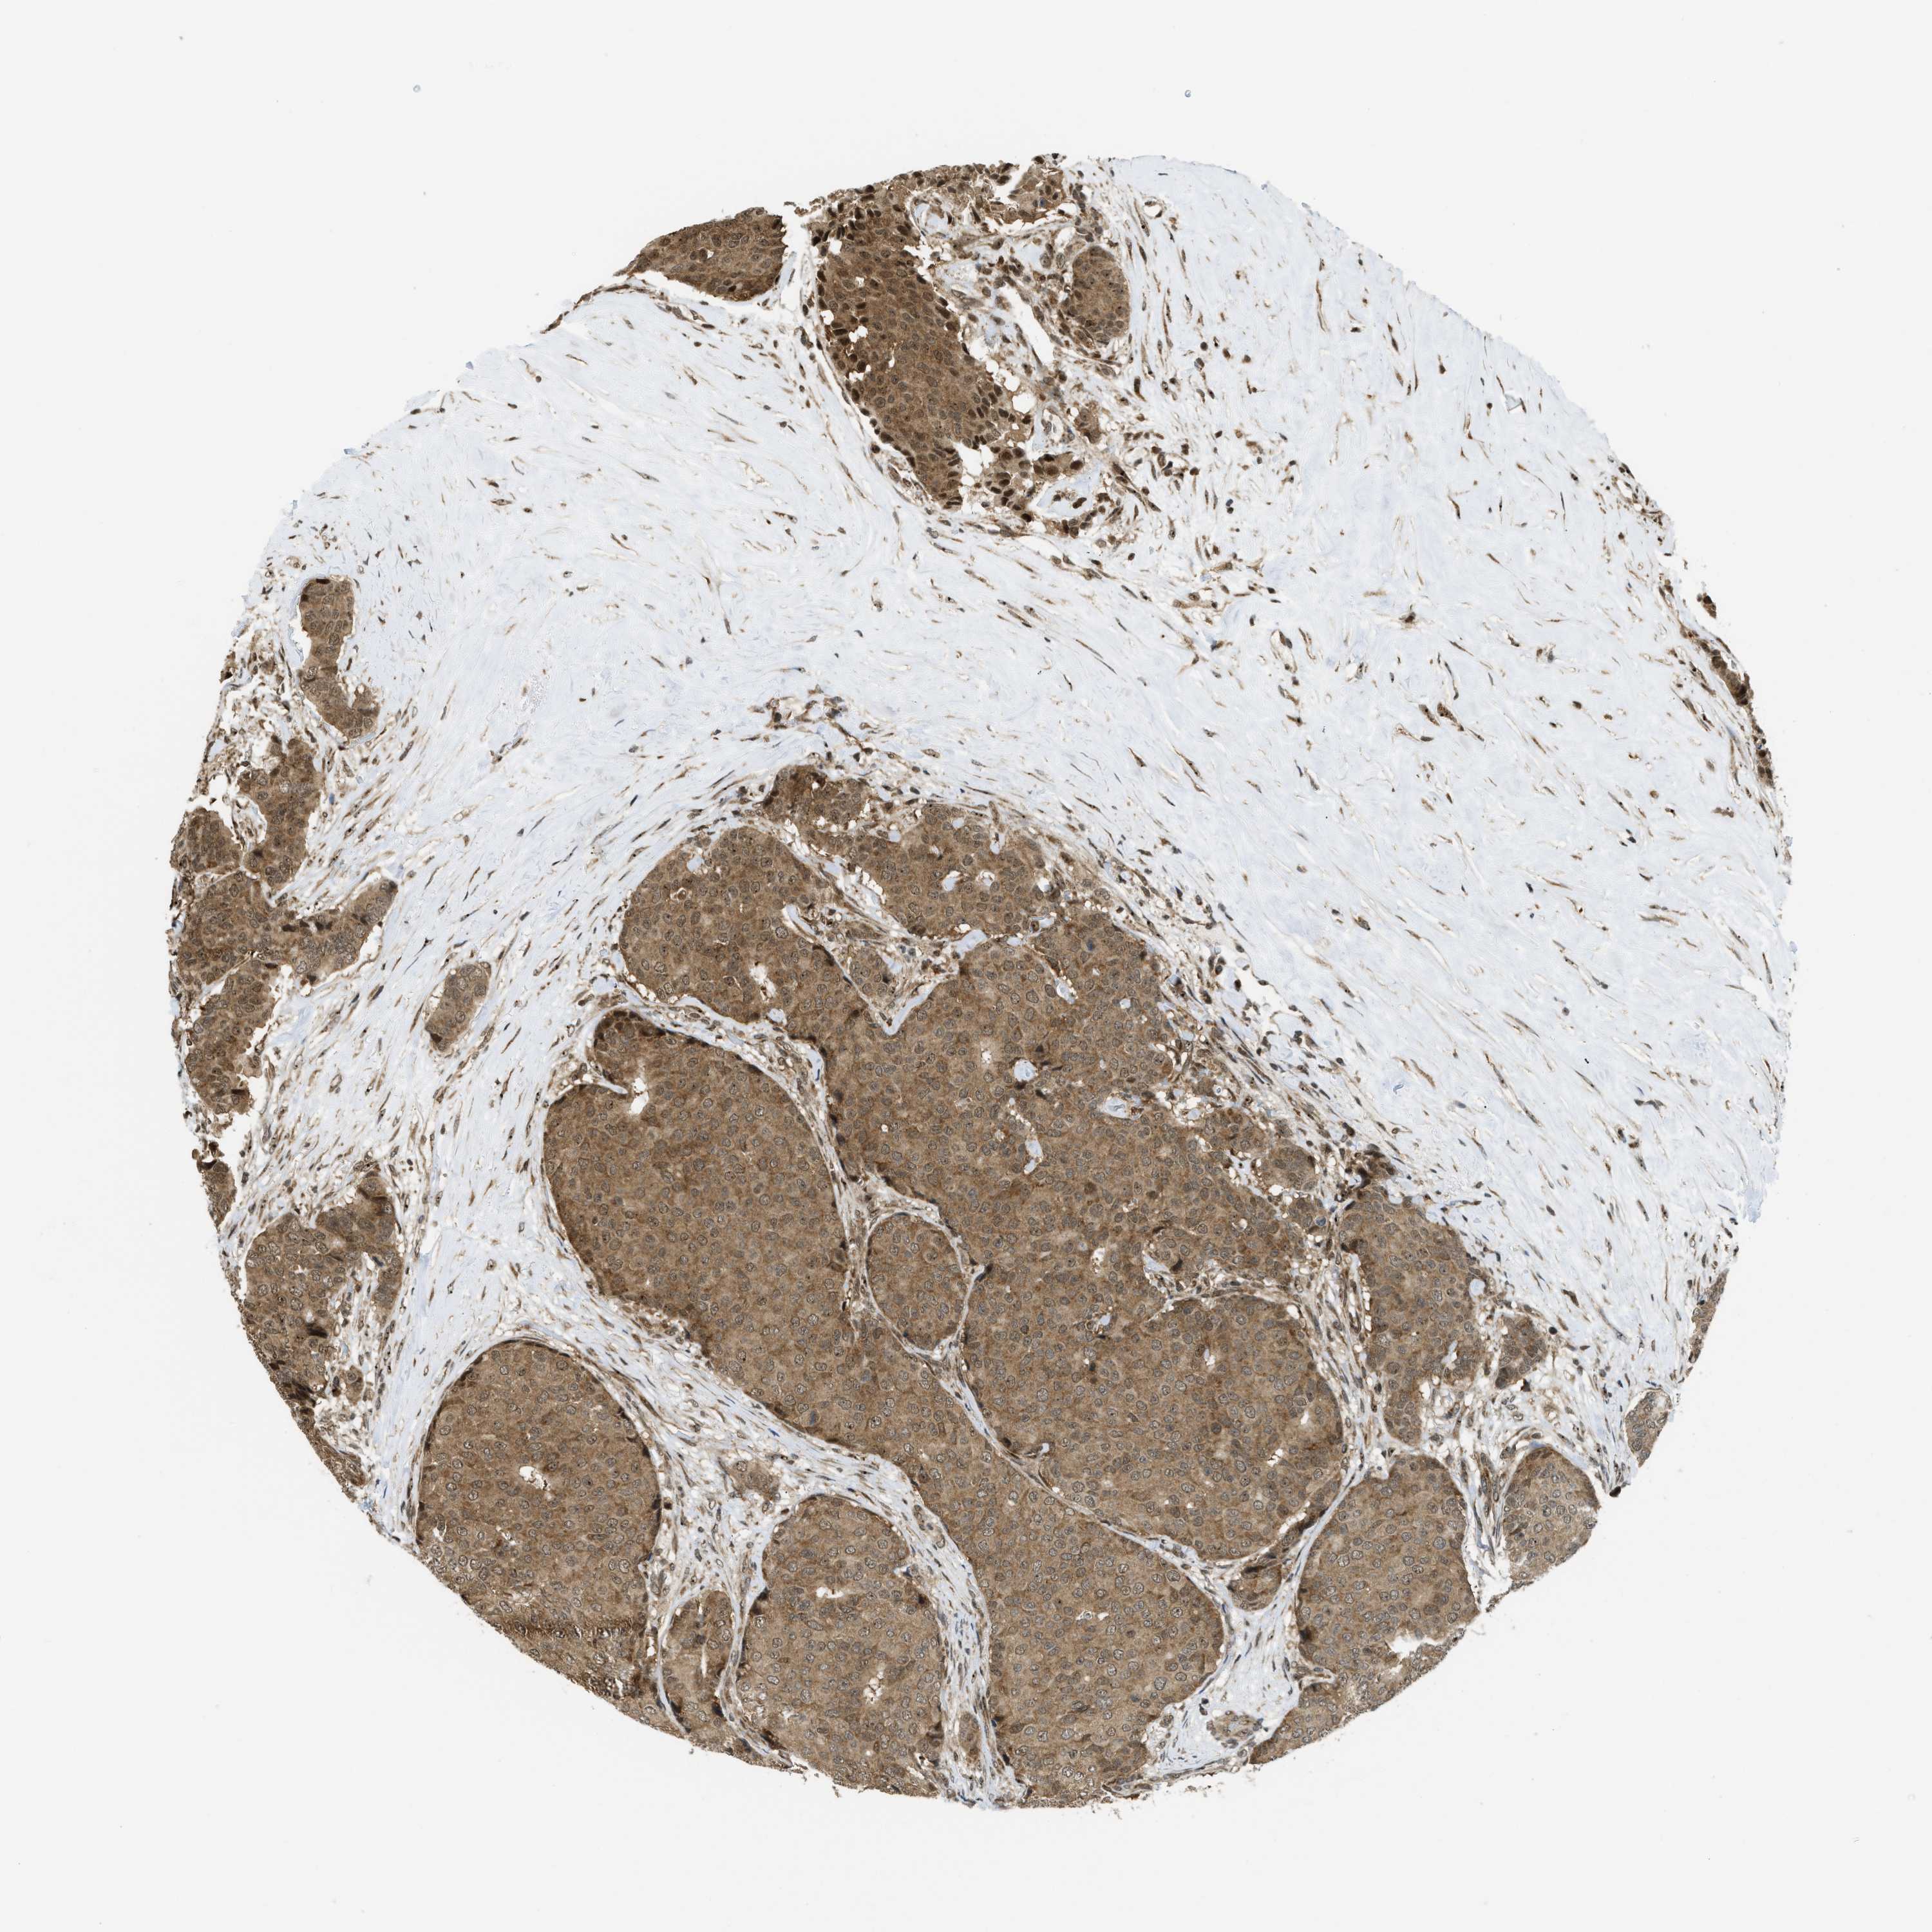

BRCA TCGA BRCA VALIDATION PROTEIN EXPRESSION